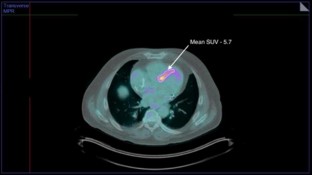

F18-FDG PET/CT with MPI was used in CS diagnosis (N = 67). Mean and max SUV were measured and grouped as basal, mid, and apical disease. Post-scan ventricular tachycardia, AICD placement, complete heart block, pacemaker placement, atrial fibrillation, heart failure, and cardiac-related hospital admissions were recorded (mean follow up 2.98 ± 2 years). Poisson regression analysis revealed that max SUV, mean SUV, as well as mean basal SUV, and LVEF were significantly associated with total cardiac events. Max SUV odds ratio (OR) = 1.068 (95% CI 1.024-1.114, P = 0.002), mean SUV OR = 1.059 (95% CI 1.008-1.113, P = 0.023), mean SUV OR = 1.061 (95% CI 1.012-1.112, P = 0.014), scan LVEF OR = 0.731 (95% CI 0.664-0.805, P < 0.001).

SUV at time of CS diagnosis has significant associations with future cardiac events. Patients with higher SUV, particularly in basal segments, are at increased risk of events. Further studies are needed to identify treatment methods utilizing risk stratification of CS.

Figure 2